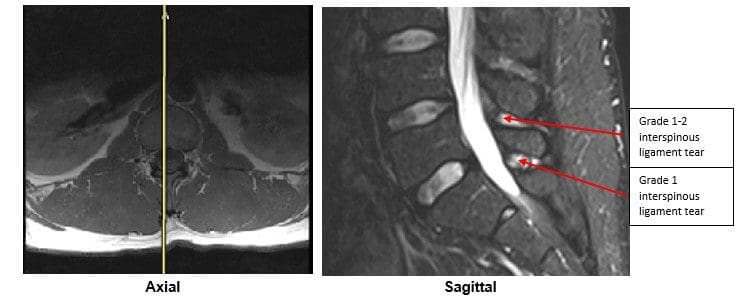

A lumbar MRI reveals;

5) L4-L5 has a Grade 1-2 tear of the interspinous ligament with mild inflammation

6) L5-S1 has a Grade 1 interspinous ligament tear with mild inflammation

In this specific case, pathology to the posterior ligament complex diagnosed on MRI lead to the x-ray finding of excessive translation at L1-L2 and L2-L3. The patient was given a permanent impairment rating of 22% based on my interpretation of the American Medical Association’s Guides to the Evaluation of Permanent Impairment, 5th Edition1. The interspinous ligament tears at the L4-L5 and L5-S1 level would not have been diagnosed without the MRI.